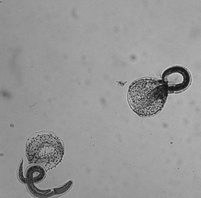

フィロフタルムス・グラリ:Philophthalmus gralliは、人獣共通感染症の吸虫の一種で、鶏の眼の結膜嚢に寄生します。

涙腺の周りまたは瞬膜の表面の下/上、眼窩に成虫の吸虫が存在すると、結膜炎、角膜炎、水様分泌物、軽度の浮腫を引き起こします。